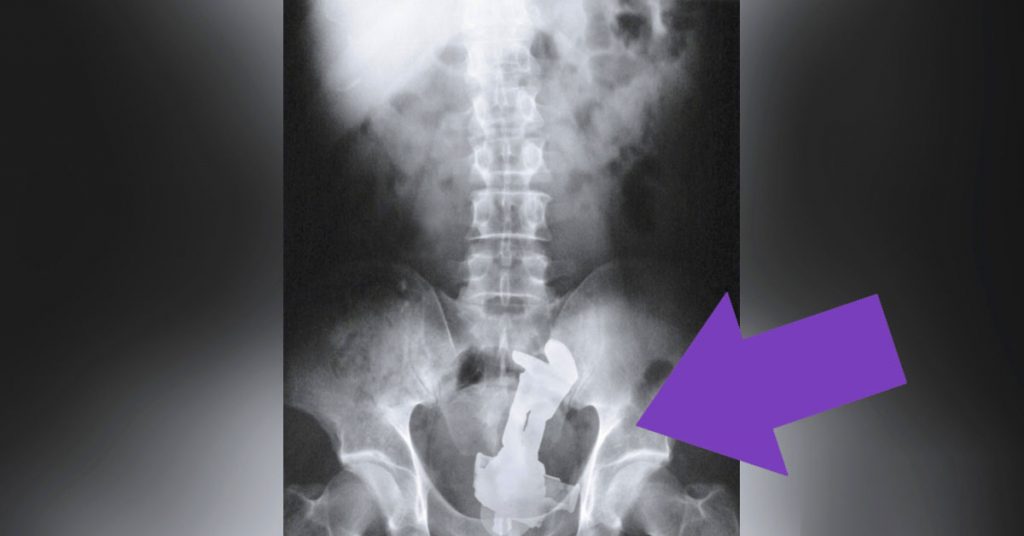

No vamos a cuestionar las motivaciones que una persona puede tener para introducirse por «cierta» parte del cuerpo algunos de los siguientes objetos que vamos a ver.

Pero de lo que sí podemos dar fe es de la veracidad de estas imágenes obtenidas clínicamente mediante el uso de Rayos-X.

Verlo para creerlo… 22 objetos que algunas personas se introdujeron en el… cuerpo.